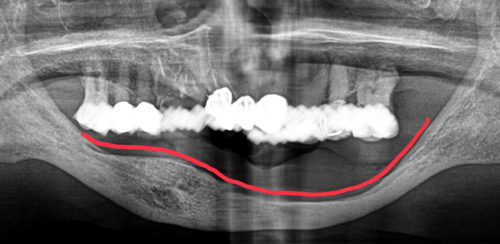

レントゲンの患者さんの顎の骨は重度に吸収し、またそれだけでなく左右差があること、

反対側(上顎)に歯があることなど、義歯を難しくしている理由はたくさんあげられます。

新しく作ればすぐに良くなるよ、と作った前医の自費の義歯が、

全然痛くて使えないそうです‥